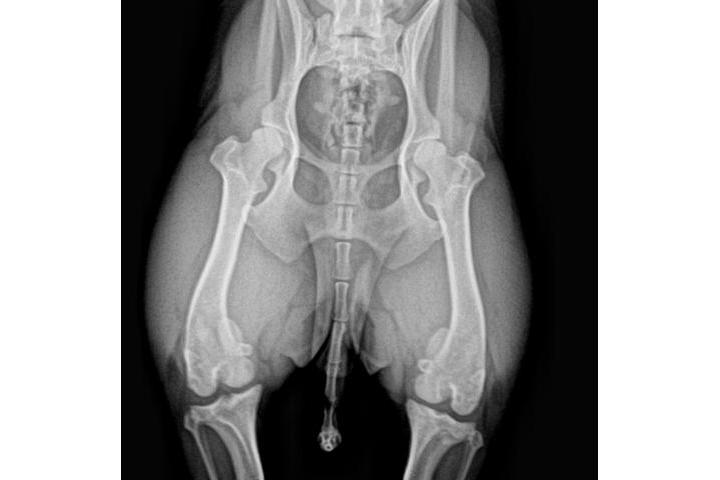

Actualisation sur la cause

Victoria Riera Serra

Teaming Manager

le 30/05/2017 à 17:52h

3a radio

Tengo buenas no tan buenas noticias...la adopción legal de Sólo se ha resuelto....ya es oficialmente nuestra....rstamos a la espera de la documentación para realizar el cambio de demarcación y censarla en Reus...por otro lado la visita al veterinario y las rx confirmaron el diagnóstico inicial...el grado de luxación de sus rótulas es muy grave y la cirugía es inevitable....estoy a la espera del informe del traumatólogo y del nuevo presupuesto para haceroslo llegar a todos; si bien es algo más económico que los dos anteriores sigue subiendo un pico. Habrá que operarprero una para y esperar para posteriormente operar la otra..de ese modo podrá llevar una vida relativamente normal hasta su total recuperación....la buena noticia es que no hay indicios de artrosis lo que significa que no hay dolor...una vez iniciado la primera intervención se valorará es estado de sus tendones para descartar un "tendón laxo"...a lo largo del día recibiré por mail el informe completo junto con una copia de las rx para poder mostraroslas....de nuevo gracias a todos por ayudarme a hacer posible el tratamiento de Snoopy